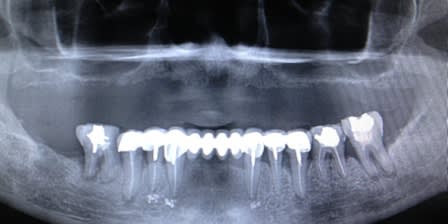

les zygomatiques, c'est autre chose.

ici, bien des pterygo.

bf, bien mené, mais c'est peut être un poil sous équipé, non?

(plaques petit modele, 3 anterieurs)

7 c'était le max possible , il n' y a rien

ci joint photo du modèle stéréo , balcon osseux ant . empechant la pose de disques